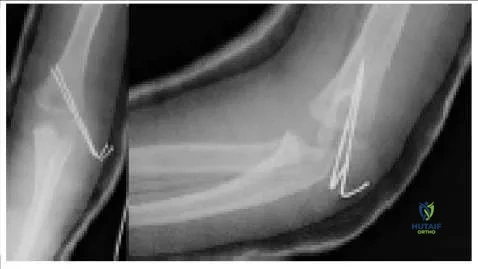

A patient had an elbow fracture that was openly reduced and internally fixed. The radiographs (Slide) from his first postoperative checkup are presented. Which of the following is a correct assessment:

Correct Answer: The two pins should have diverged in the proximal fragment.

This patient has a lateral condyle fracture. This type of fracture has a tendency to spread unless adequate compression is maintained. Diverging pins in the proximal fragment is the most widely advocated strategy.